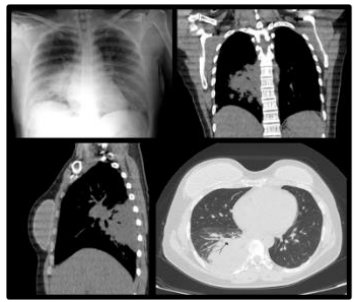

Paciente do sexo feminino, 41 anos de idade apresentou dor

torácica à direita, com 3 dias de evolução. Nesse período, houve

febre, mal-estar, astenia, mialgia e piora da falta de ar, o que a

motivou a procurar a emergência de um hospital. Foi admitida

com sinais vitais normais. Foram solicitados exames

complementares.

Três horas após admissão hospitalar iniciou quadro de palidez cutânea, extremidades frias, hipotensão (60X40mmHg), taquipneia (32 irpm), dessaturação (Sat O2 89%), falta de ar e fraqueza. Gasometria revelou acidose metabólica com alcalose respiratória compensatória (PH 7,42 | PCO2 23 | PO2 102 | HCO3 14,6 | BE -8,7 | LAC 5,5 | SATO2 97%). Exames laboratoriais com os seguintes resultados: HB 9,4 | HT 28,6 | LEUCO 11.250 | PLAQ 182.000 | K 3.8 | NA 133 | CR 1,14 | U - | LDH 403 | PCR 10,4 | Ca 8,2.

Foi providenciado acesso venoso profundo, hidratação vigorosa, prescrição de bicarbonato, oxigênio sob máscara de alto fluxo. Houve evolução clínica satisfatória com estabilização dos sinais vitais. Nova gasometria foi realizada 6 horas após: PH 7,44 | PCO2 32,3 | PO2 106,4 | HCO3 21,6 | BE -2 | LAC 4,27 | SATO2 97,4%.

Telerradiografia e tomografia computadorizada do tórax revelaram as imagens a seguir.